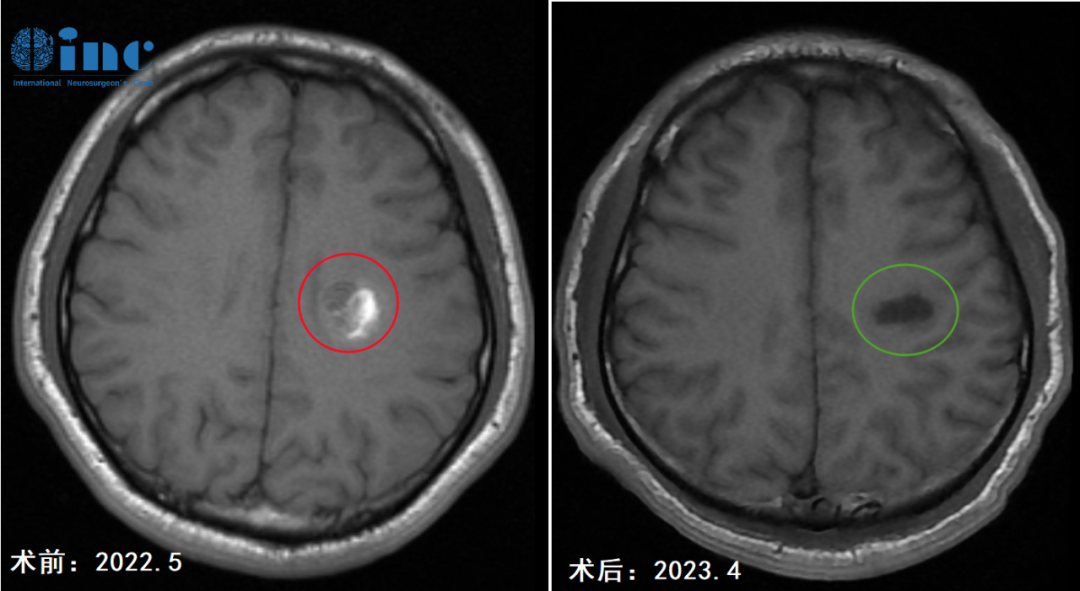

准备工作结束后,斌斌的半卵圆中心海绵状血管瘤开颅手术正式开始。几小时的持续奋战,在术中导航和神经电生理监测的双重护航下,巴教授顺利顺利全切斌斌的半卵圆中心海绵状血管瘤。

▼术前术后MRI影像对比